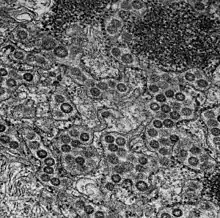

Les MRC-5 sont une lignée de cellules de type fibroblastes embryonnaires humains obtenue à partir d'un unique fœtus avorté en 1966 [1]. Elles sont utilisées pour réaliser des cultures de virus (par exemple le Cytomégalovirus), à des fins de diagnostic, de recherche ou pour produire des vaccins comme celui contre l'hépatite A[2]. Le fait que ces cellules descendent de cellules de fœtus avortés entraîne une controverse sur la vaccination[3].

Cellule MRC-5